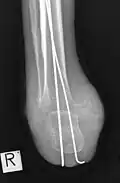

Der operative Zugang für die Amputation erfolgt von vorn (ventral), mit Bildung eines weiter nach distal reichenden Sohlenlappens, der dann den ventralen Defekt decken kann und auch dort eine Endbelastungsfähigkeit herstellt. Die Haut des Fußrückens ist hingegen sehr druckempfindlich und dort, wo durch die Belastung oder die Prothese Druck entsteht, gefährdet. Nach Darstellung des Sprungbeins wird dieses komplett entfernt (Astragalektomie). Die Gelenkfläche des oberen Sprunggelenks wird zusammen mit Innen- und Außenknöchel durch eine horizontale Osteotomie mit einer oszillierenden Säge reseziert, unter besonders sorgfältiger Schonung der hinter dem Innenknöchel verlaufenden Gefäße. Anschließend erfolgt auch am Fersenbein eine horizontale Osteotomie, wodurch alle Gelenkanteile des subtalaren Gelenkes entfernt werden. Durch die Entfernung des Sprungbeins werden etwa 3 bis 4 cm Platz gewonnen, sodass auch eine starke Achillessehnenverkürzung hierdurch in der Regel bereits ausgeglichen ist und eine Sehnenverlängerung selten notwendig ist. Die Entfernung der Malleolen erfolgt für eine gute Prothesenversorgung. Die calcaneotibiale Arthrodese erfolgt unter Kompression und mit einem Vorschub des Fersenbeins um etwa 10 bis 15 mm, wobei das Fersenbein in einer leichten Außendrehung wie auf der Gegenseite eingestellt werden muss. Anschließend ist eine Abrundung der distal-plantaren Fersenbeinkante vor allem an der Außenseite notwendig, um keine druckempfindliche knöcherne Prominenz zu erzeugen. Als Osteosynthese wird meist ein Fixateur externe mit jeweils zwei Steinmann-Nägeln oder langen Schrauben in Tibia und Calcaneus eingesetzt, alternativ gekreuzte K-Drähte, die von proximal durch Tibia und Calcaneus eingeführt werden und dadurch die Sohlenhaut nicht verletzen. Ein Hautschluss muss spannungsfrei erfolgen.[1]